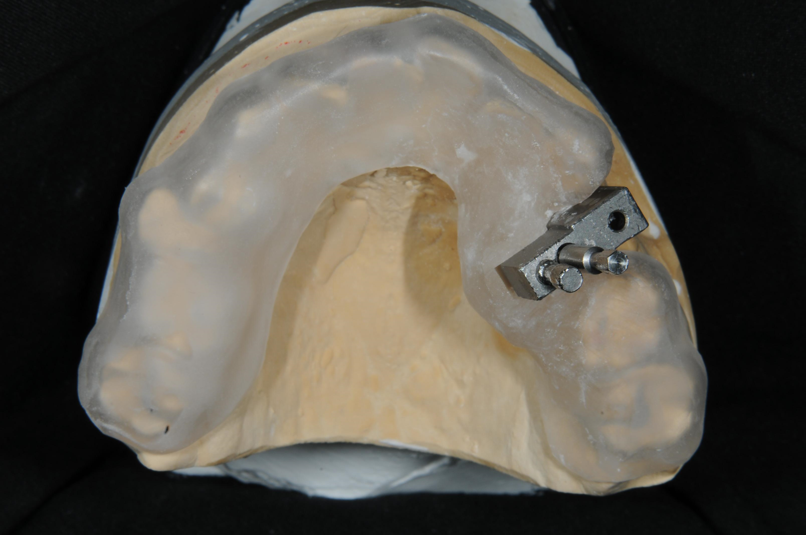

模型上咬合器

植牙印模與上咬合器